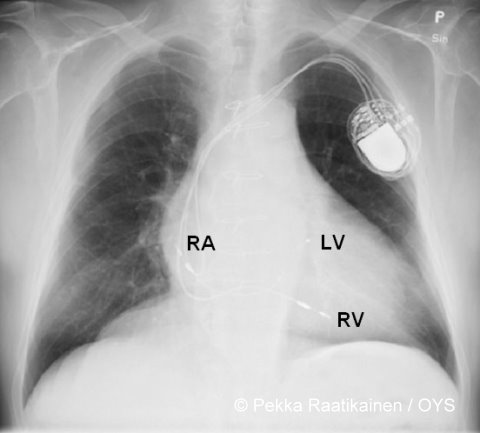

Heart failure pacemaker.Chest x-ray depicting a biventricular cardiac pacing system used for the treatment of cardiac failure. The atrial lead (RA) is in its usual location in the right atrium and the ventricular lead (RV) is in the apex of the right ventricle. The unipolar lead (LV) used for pacing of the left ventricle is guided through the coronary sinus and positioned posteriorly on the surface of the left ventricle.

Picture: Pekka Raatikainen